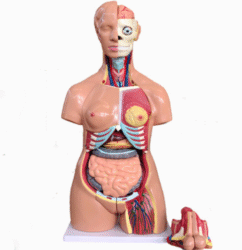

ATL-11 MALE MUSCLES FIGURE INTERNAL ORGANS HARD

The model is an anatomically accurate representation of the human anatomy, complete with superficial and deep musculature, the digestive system, lymphatic system, respiratory system, urinary system, circulatory system, endocrine system, and nervous system. Our model has removable organs and dissectible features for a complete educational experience.

Classification: